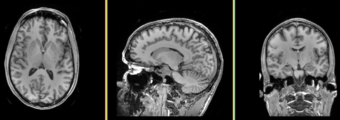

=Result= | =Result= | ||

Image:MRIHumanBrainFullParcellationT1.png | Image:MRIHumanBrainFullParcellationT1.png | ||

Single channel automatic segmentation of t1w-MRI brain scans into the major tissue classes (gray matter, white matter, csf). The task can only be applied to t1w brain scan showing parts of the skull and neck. The pipeline consist of the following steps: